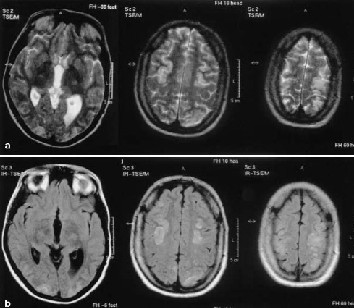

宾斯旺格病的发病机制不明,Schmidt对273例老年人进行为期3年的随访研究,通过MRI观察脑白质异常变化,发现49例(17.9%)有脑白质改变。推测本病的基因作用约占73%,引起脑白质改变的基因,可能与高血压基因相关,Apo E和超氧化酶基因可能是脑白质病变的危险因素。

病理改变:脑沟和脑回大致正常,可见中、重度动脉粥样硬化,脑切片病变主要累及脑白质,可见白质萎缩、双侧脑室扩大、脑室旁白质多发腔隙性梗死灶,有时可见胼胝体变薄。镜下可见大脑、脑桥、基底核等小动脉丰富处白质空泡样变性,伴有髓纤维数量减少。半球深层白质动脉和小动脉特别是穿髓小动脉呈玻璃样变性,深层白质髓鞘脱失主要位于枕叶、颞叶及与额叶联系纤维,皮质和皮质下U形纤维保留完好,胼胝体常不受累。